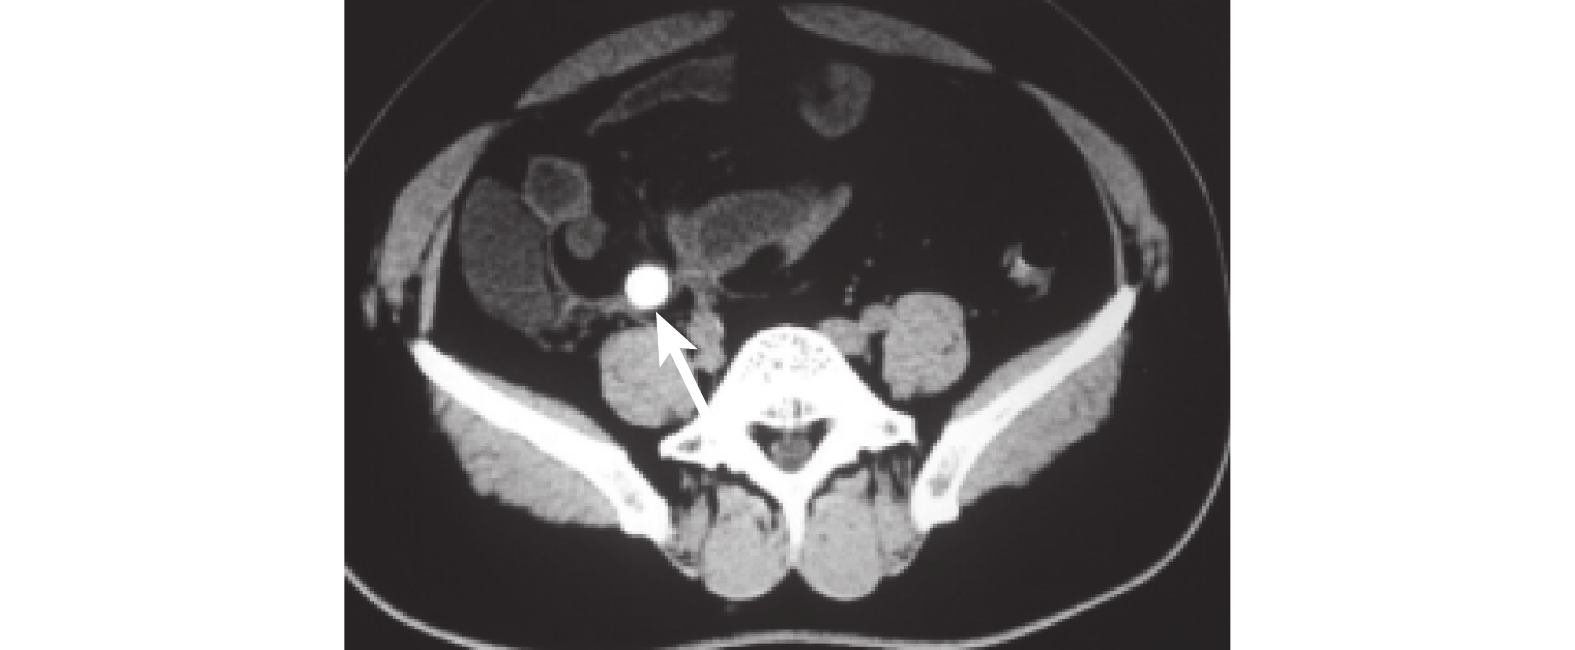

本組 60 例患者的 CT 影像學的主要表現為:闌尾增粗、管壁增厚 41 例,回盲部結構紊亂、周圍脂肪間隙不清、闌尾內有高密度糞石影 19 例,壞疽穿孔性闌尾炎可有腹腔散在氣體影 2 例,周圍腸管可有管壁增厚、積氣和積液 1 例,盆腔膿腫 1 例,伴有小腸梗阻 1 例,共有 5 例患者盲腸周圍可見少量游離氣體影。有 6 例患者的闌尾解剖異常,包括 2 例肝下闌尾、3 例腹膜后位闌尾及 1 例盆腔闌尾。所有患者均行腹腔鏡或剖腹探查手術治療,術后病理學檢查結果證實為急性闌尾炎 59 例,輸卵管感染積膿、膿液包裹闌尾 1 例,CT 檢查的診斷符合率為 98.3%。典型病例見圖 1~8。

文獻[2]報道,急性闌尾炎的 CT 影像學改變為:闌尾直徑>6 mm、闌尾壁厚度>2 mm,有糞石、異常強化等。闌尾最常見的位置是下降腹腔內[12],急性闌尾炎患者的典型腹部 CT 表現為闌尾異常、闌尾周圍炎和盲腸末端改變,其中闌尾異常包括闌尾增粗(>6 mm)、管壁增厚(>2 mm)、管狀結構顯示不清、闌尾腔內可見糞石影,闌尾壁可呈同心圓樣改變,增強掃描可見闌尾壁強化等[13]。除此之外,若發生壞疽或膿腫,CT 可見盲腸壁增厚且淋巴結增大的情況[14]。若闌尾穿孔,則闌尾周圍可見氣體影,有助于進一步鑒別診斷是否為穿孔性闌尾炎[15]。本組病例中有 41 例患者的 CT 表現為闌尾增粗和管壁增厚,19 例患者表現為闌尾內糞石樣高密度影,2 例壞疽性闌尾炎患者 CT 表現出腹腔散在氣體影(此應注意與消化道穿孔鑒別),也有患者僅表現為盲腸周圍結構紊亂、脂肪間隙密度高及條索狀影。

闌尾糞石對診斷急性闌尾炎有相當重要的意義。本組 19 例患者在 CT 下可見闌尾糞石,當發現闌尾糞石同時合并闌尾周圍炎時,是診斷急性闌尾炎的可靠指征[16]。如有闌尾糞石伴盲腸周圍炎可診斷急性闌尾炎,但是如果只有盲腸周圍炎而未見到闌尾糞石,則只能懷疑診斷急性闌尾炎。